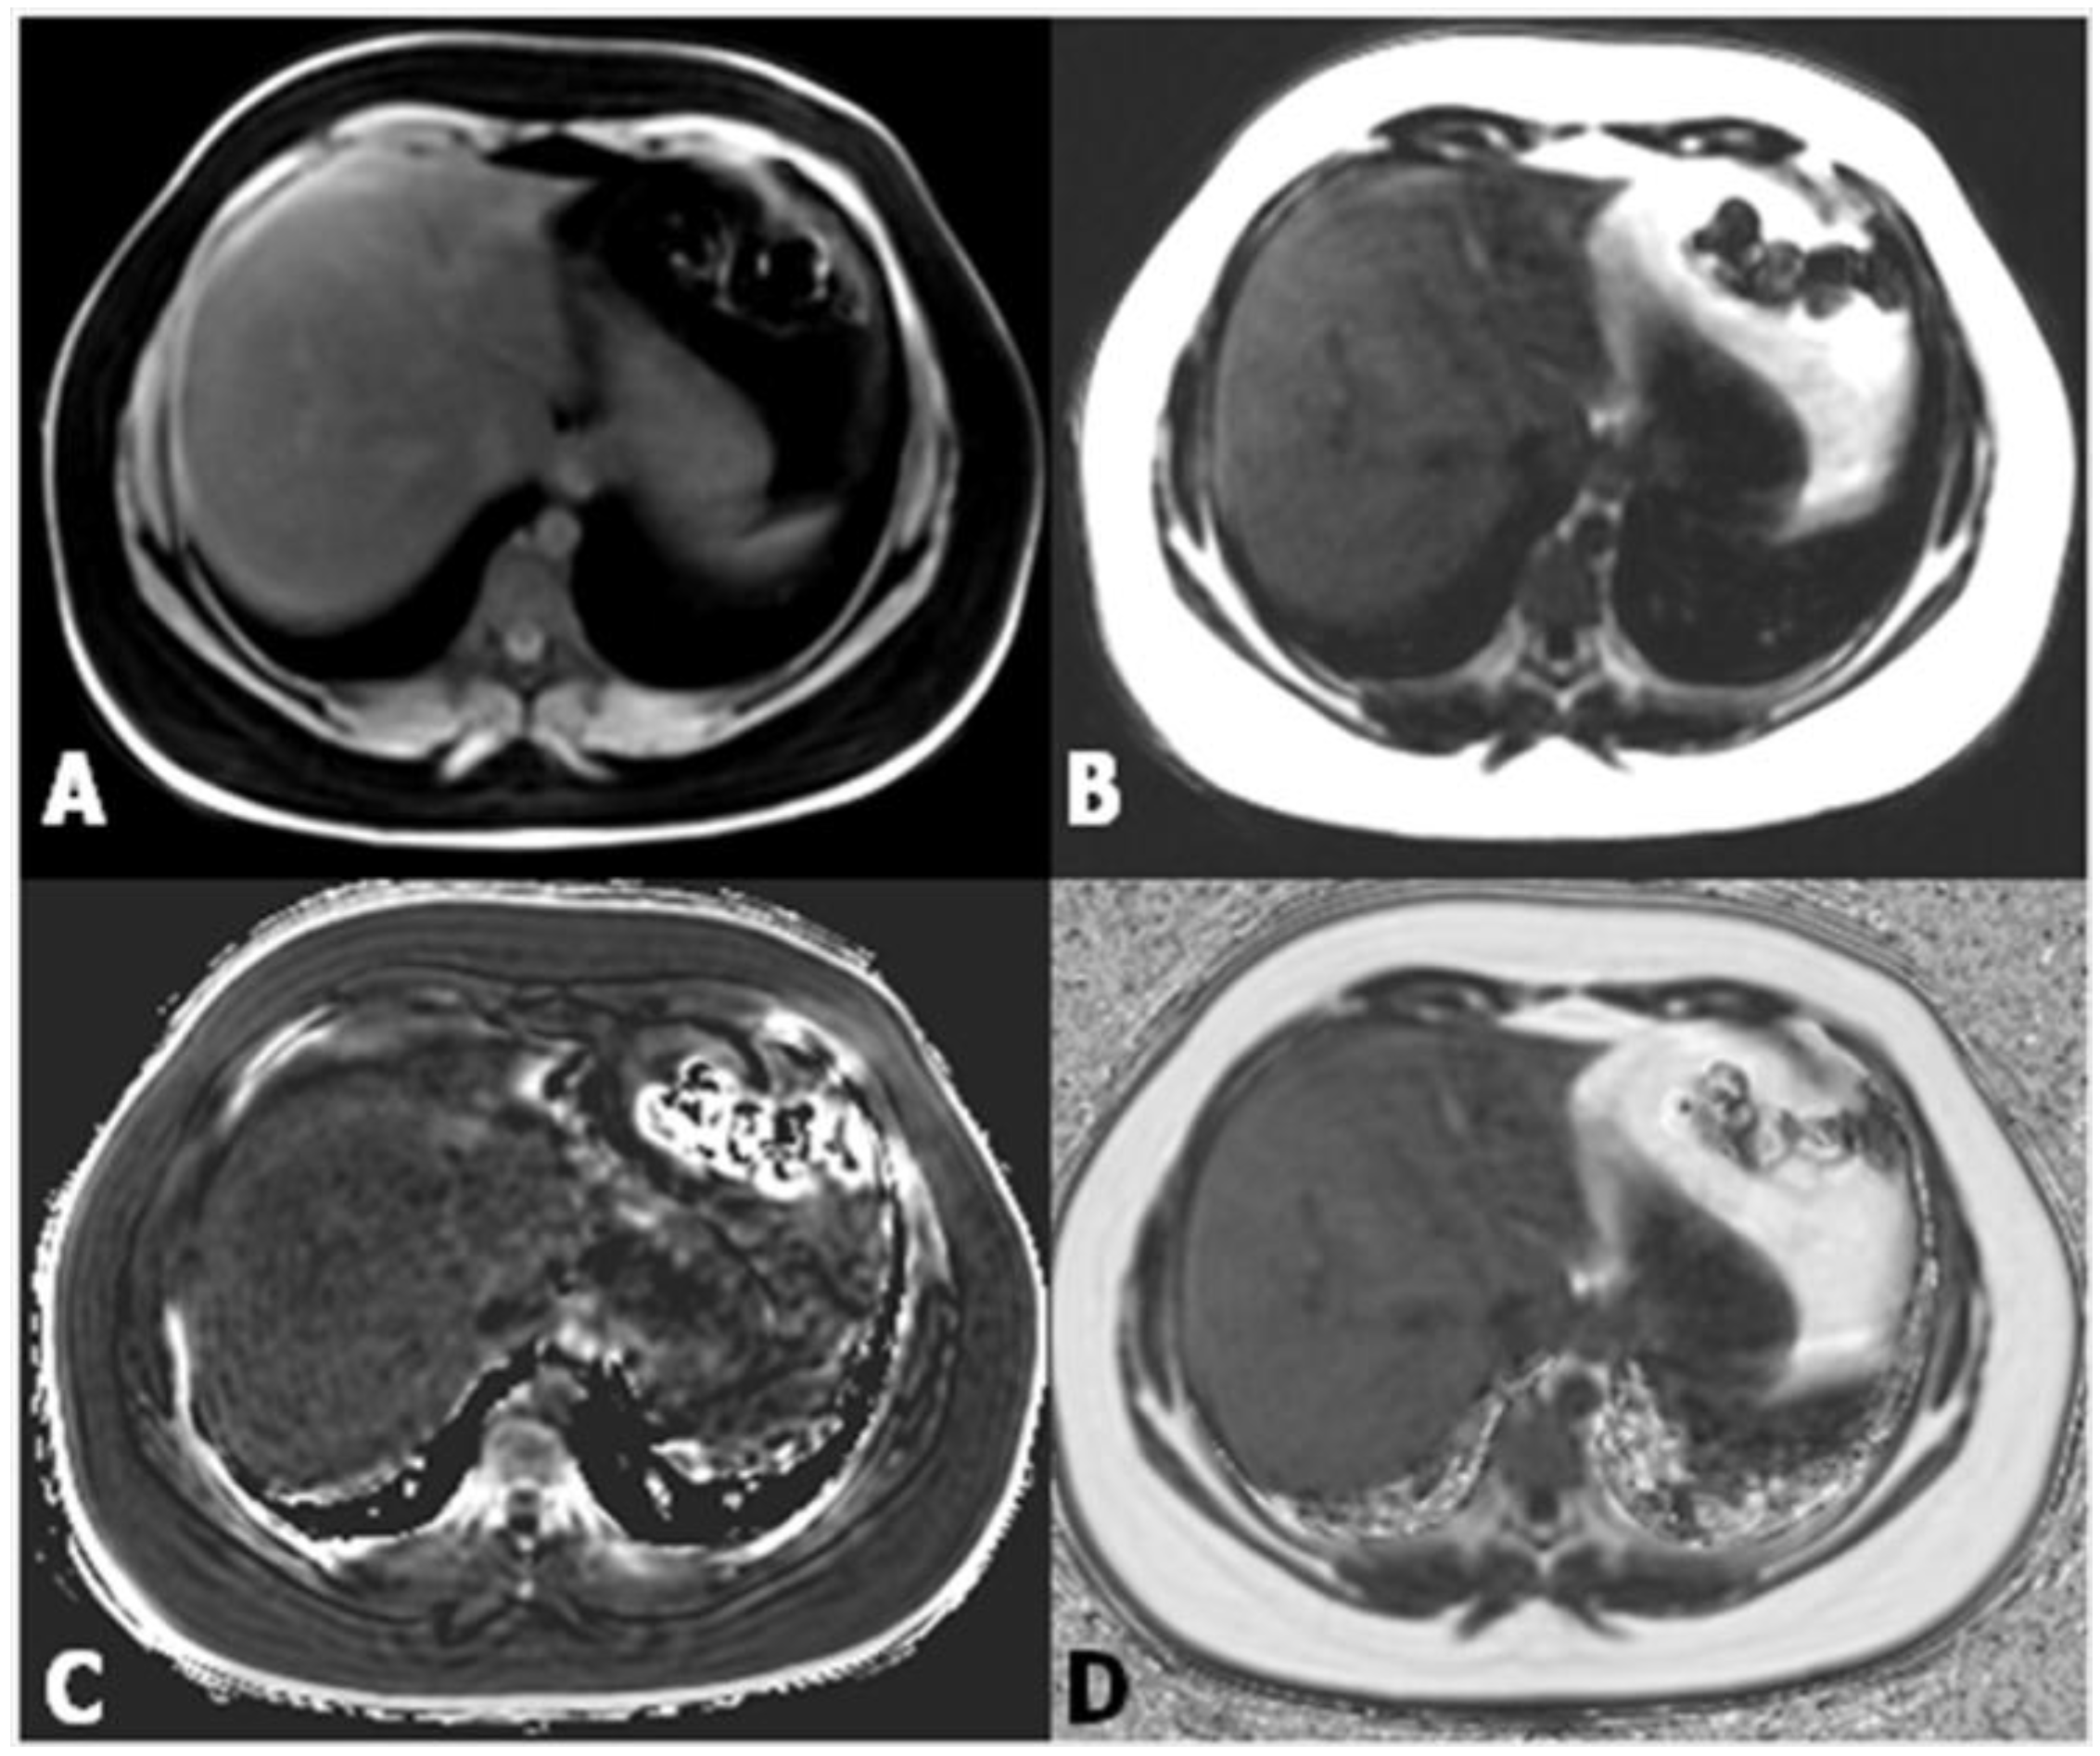

3. Magnetic Resonance

Magnetic Resonance Elastography